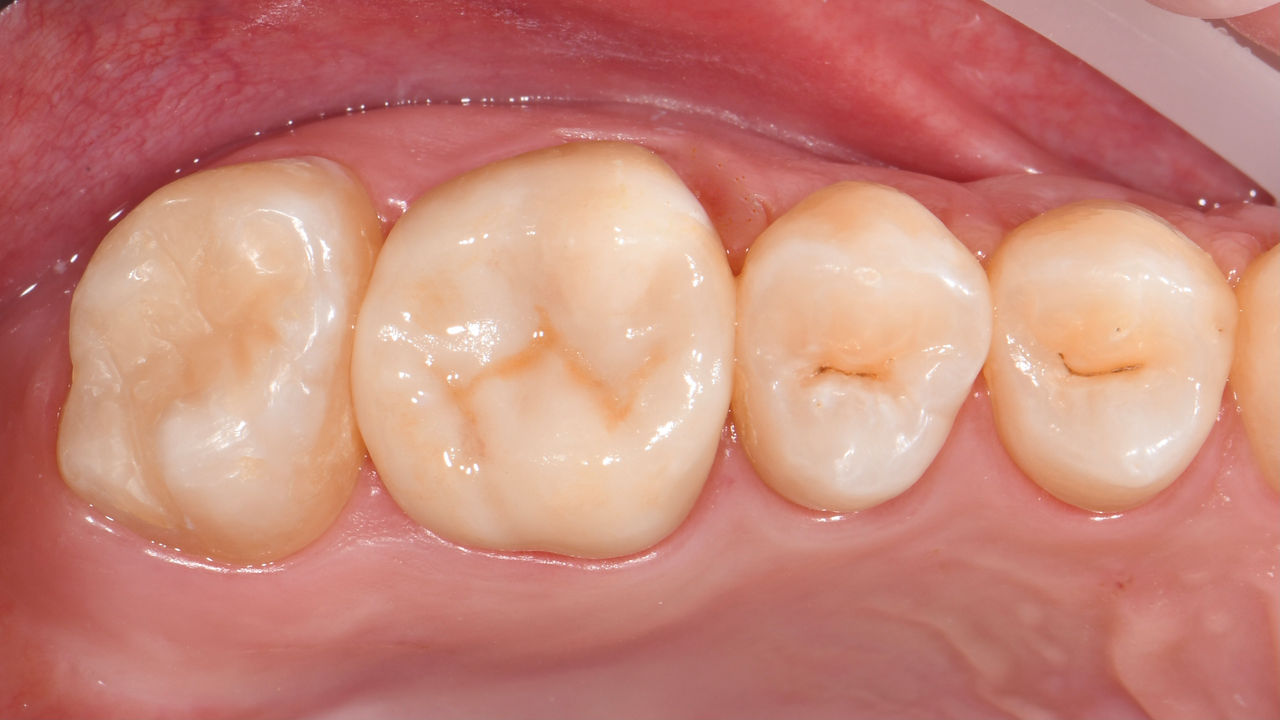

Before: Pre-operative clinical scenario after endodontic therapy.

After: 1 month after the CEREC Tessera onlay was bonded.

Second lower right molar in 90 minutes

A CEREC Tessera onlay

A 20-year-old female patient had endodontic treatment of her lower right 2nd molar. A chairside onlay was fabricated from the new high-strength ceramic CEREC Tessera ALD.